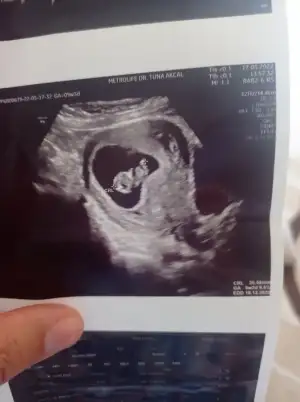

prenses gibi12+6 karından ultrason

Bana bakarmisiniz rica etsem9 hafta 2 günlük karından bakildi

Bana da bakarmisiniz 9+2 karindankarındansa prenses gibi![]()